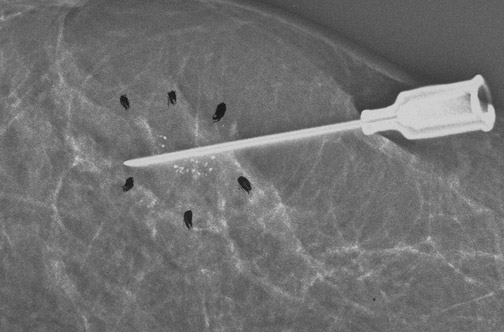

The mammogram above demonstrates the use of needle localization to aid the surgeon in excising the suspicious area, in this case the area with the microcalcifications.